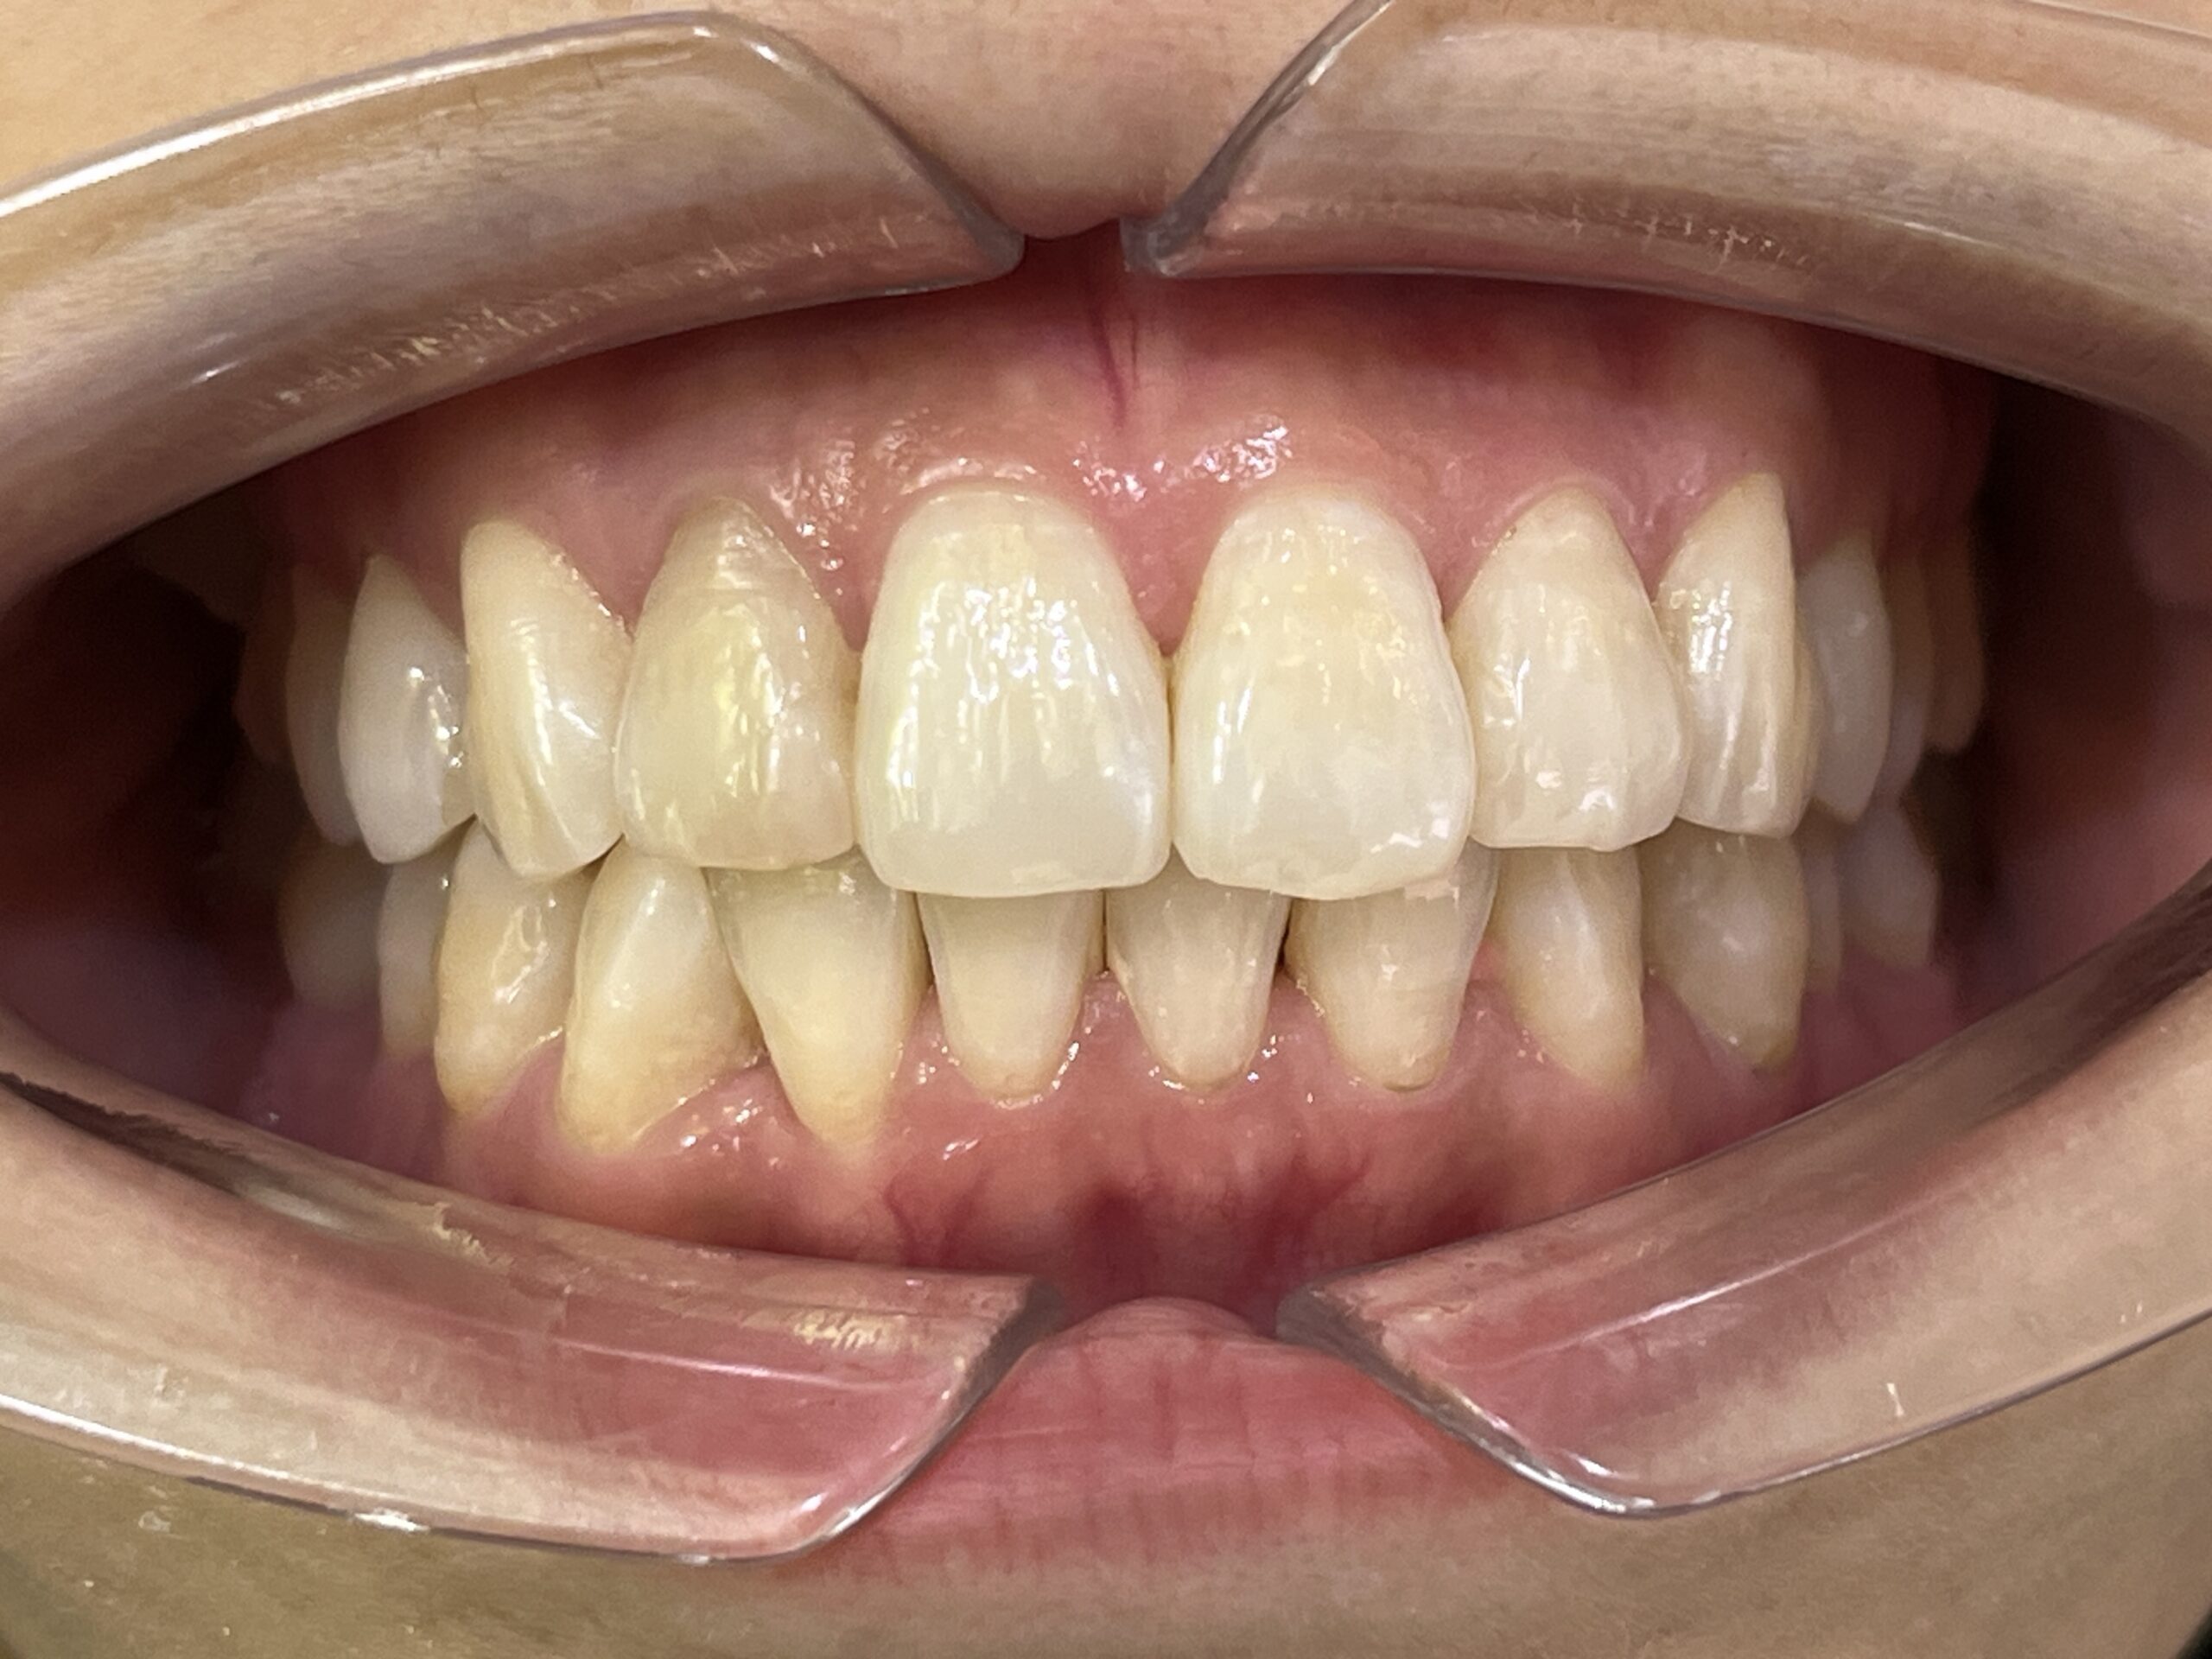

叢生の症例3(マウスピース矯正)

治療前後(BEFORE/AFTER)

| 年齢 | 10代女性、叢生、八重歯 |

| 主訴 | 八重歯、歯のガタガタ |

| 診断 | 叢生 |

| 治療方法 | 上下・マウスピース矯正(抜歯はしていません) |

| 治療期間 | 約2年 |

| 費用総額 | 1,100,000円(税込) |

| リスク・副作用 | 痛み/歯根吸収/歯肉退縮/後戻り など |

本症例では八重歯がかなり出ている叢生状態でした。

下顎前歯のガタガタも併せて治したいというご希望でした。

抜歯も検討しましたが、スキャナーによるシミュレーション、精密検査により歯列のスペースを確保しかみ合わせも意識しながら歯並びを整えるため、抜歯をしないで矯正治療を行いました。

思春期で難しいながらもマウスピース矯正で行い治療後は歯並びとかみ合わせが改善し、

見た目だけでなく歯磨きもしやすい状態になりました。